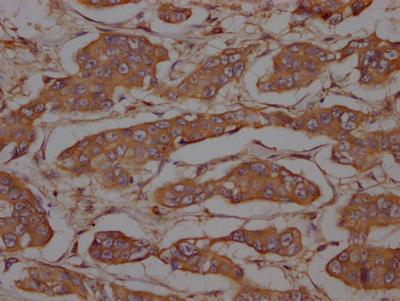

CSB-RA260392A0HU

IHC image of CSB-RA260392A0HU diluted at 1:100 and staining in paraffin-embedded human breast cancer performed on a Leica BondTM system.

CSB-RA634199A0HU

IHC image of CSB-RA634199A0HU diluted at 1:100 and staining in paraffin-embedded human breast cancer performed on a Leica BondTM system.